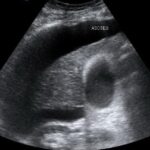

Difference Between Ascites and Edema

Difference Between Ascites and Belly Fat

Difference Between Ascites and Bloating